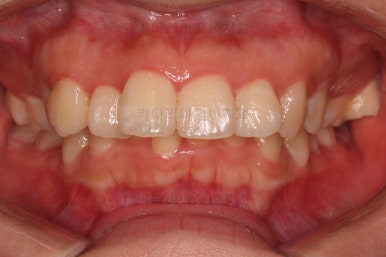

부산무턱교정치과 초진 시 입안의 모습입니다.

전반적으로 치열이 삐뚤고요. 아랫니가 윗니보다 뒤쪽으로 많이 가려져 있죠.

그래서 앞에서 봤을 때 아래 앞니가 거의 보이지 않는 상태인데요.

이런 교합을 "과개교합"이라고 표현합니다.

전반적인 교합, 치열, 과개교합, 튀어나와 보이는 앞니 등을 개선해줘야겠네요.